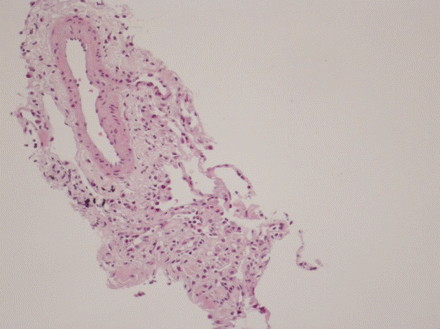

Exame citológico do líquido da lavagem broncoalveolar, revelando a presença de uma grande predominância de eosinófilos (A), representando 27% dos elementos celulares. Os outros elementos celulares encontrados foram macrófagos (C) e linfócitos (B)

BMJ Case Reports 2009; doi:10.1136/bcr.04.2009.1731. Copyright © 2011 by the BMJ Publishing Group Ltd